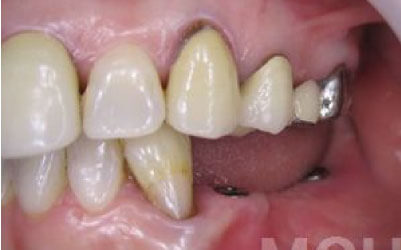

ブリッジ治療では、失われた歯の役割を両隣の歯が補うことになるため、その支えの歯には通常の1.5〜2倍ほどの力がかかるとされています。

ブリッジ治療では、欠損部分の両側にある歯を大きく削らなければならず、場合によっては虫歯がなくても歯の神経を抜くことがあります。神経を抜いた歯に被せ物をすると、その歯は急速に弱くなり、寿命が短くなるリスクが高まります。

残っている歯にとって、ブリッジ治療は非常にリスクが高い方法です。

その理由は、ブリッジを作るために隣接する歯を大きく削らなければならないからです。

場合によっては、その歯の神経を取ることもあります。それだけ歯に負担をかけるため、歯の寿命が急激に縮んでしまいます。

最も大きな違いは、前後の歯の寿命に影響が出ることです。

ブリッジの場合、抜けた歯の前後にある歯を、重度の虫歯と同じくらいまで削る必要があります。

また、抜けた歯の代わりに前後の歯が力を支えるため、その歯に常に1.5倍の負荷がかかります。

1)ブリッジ

2)歯を大きく削る+支えの歯に1.5倍の力がかかる

3)前後の歯の寿命が著しく減る

ブリッジの支えの歯は、データでは10年以内に68%が抜歯になります。